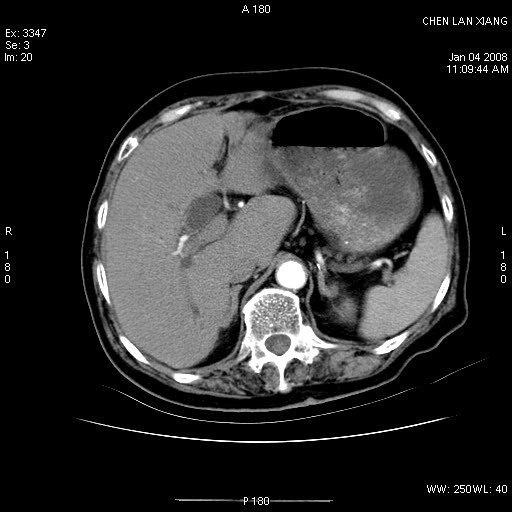

女,76岁,腹痛3-4天,b超示:肝内实性肿物,胆囊强回声,胆总管扩张.

考虑:1、胆总管下端结石伴梗阻性肝内外胆管扩张(肝左叶外侧段肝内胆管多发结石、胆管炎);

2、肿囊癌累及肝,不除外 黄色肉芽肿性胆囊炎。

1 胆总管末端结石伴肝内胆管结石,肝内外胆管扩张。2 胆囊扩大,胆囊壁不规则增厚,内见软组织密度影。考虑:慢性胆囊炎,不除外胆囊癌!

胆囊内结增强影,肝内胆管、胆总管扩张明显。肝内胆管、胆总管下段多发结石,胆囊癌,建议mrcp检查

胆囊密度增高,增强后周边肝组织及胆囊窝下部周边软组织延时性不规则强化.然胆囊壁未见明显不规则增厚及肿块.左侧肝内胆管及胆总管下段结石伴胆系扩张.

考虑;胆囊炎(黄色肉芽肿性胆囊炎?),左侧肝内胆管及胆总管下段结石.

1)胆囊癌伴肝脏转移。2)胆总管下端结石、肝内胆管结石伴肝内外胆管扩张。